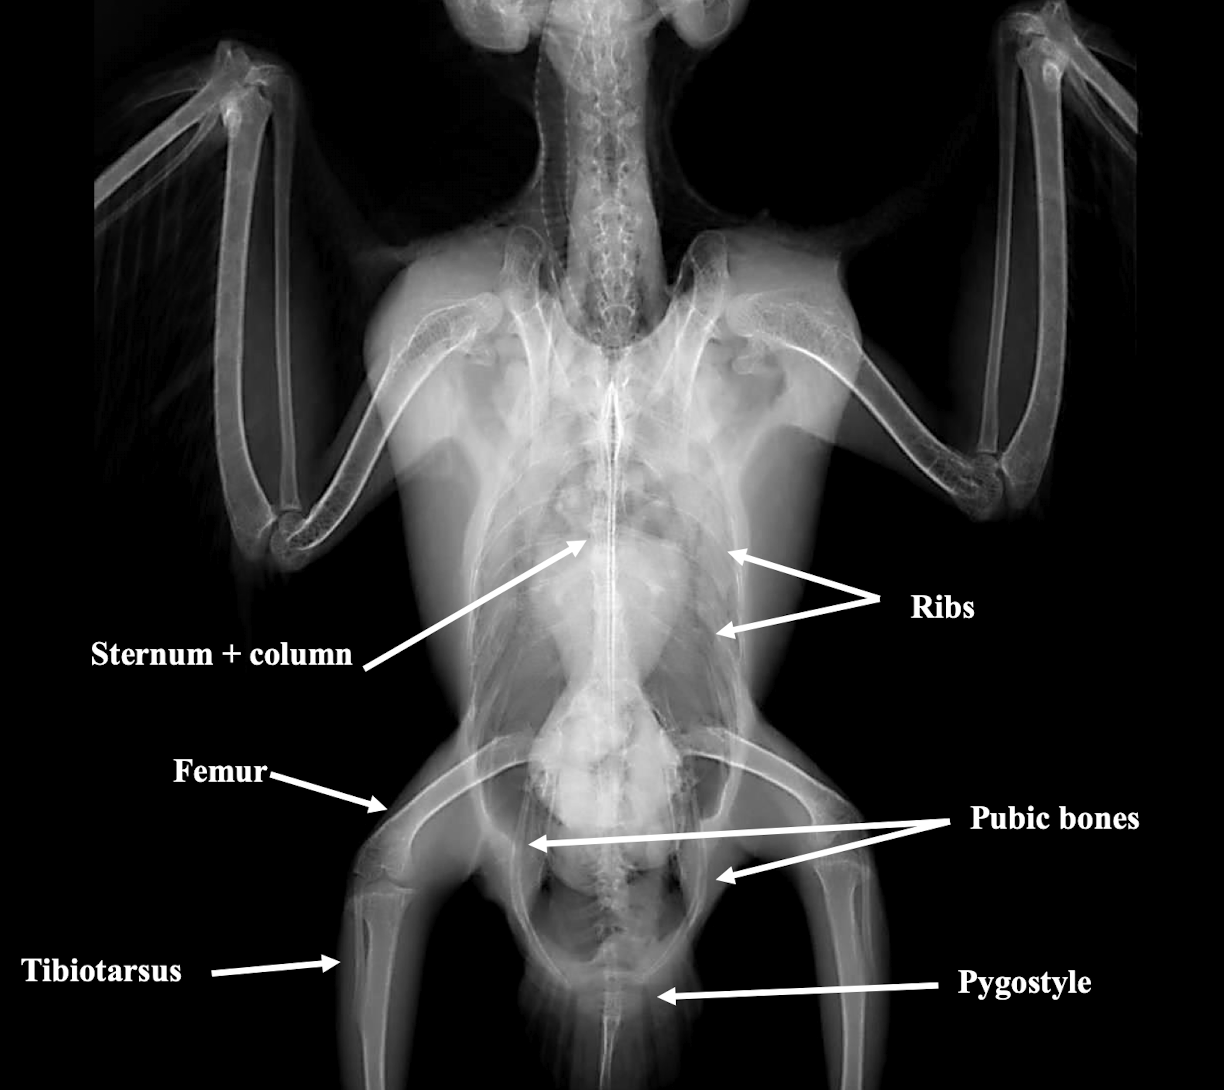

Normal avian body xray

What is important to consider regarding avian radiographic anatomy?

Knowledge of avian radiographic anatomy is important as it cannot be extrapolated from mammals due to anatomic diversity.